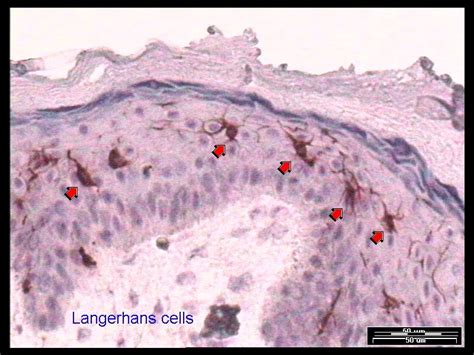

Merkel cells in the mammalian glabrous skin are always in the basal layer of the epidermis (figures 1 and 2).

Merkel cell carcinoma (mcc) is an unusual primary neuroendocrine carcinoma of the skin. Merkel cells are most concentrated in the fingertips, lips, and face, but mcc cells are most likely to develop on the head, neck, and other areas that have received the most sun. Assessment | biopsychology | comparative | cognitive | developmental | language | individual differences | personality | philosophy | social | methods | statistics | clinical | educational | industrial | professional items | world psychology |. Mcc is a fatal disease, and patients have a poor chance of survival. It's a type of skin cancer that occurs when cells in the skin, known as merkel cells, grow uncontrollably. Moreover, mcc lacks distinguishing clinical features, and thus by the time the diagnosis is made, the tumour usually have metastasized. Mccs are dermally based tumors composed of small uniform round blue cells arranged in anastomosing cords, bands and clusters. The cancer usually presents as a single reddish or purple lump on a part of the skin that is often exposed to. The tumour forms sheets, nests and rarely ribbons. Showing 20 of 480 results. View merkel cells research papers on academia.edu for free. Merkel cells in the mammalian glabrous skin are always in the basal layer of the epidermis (figures 1 and 2). Archives of histology and cytology.